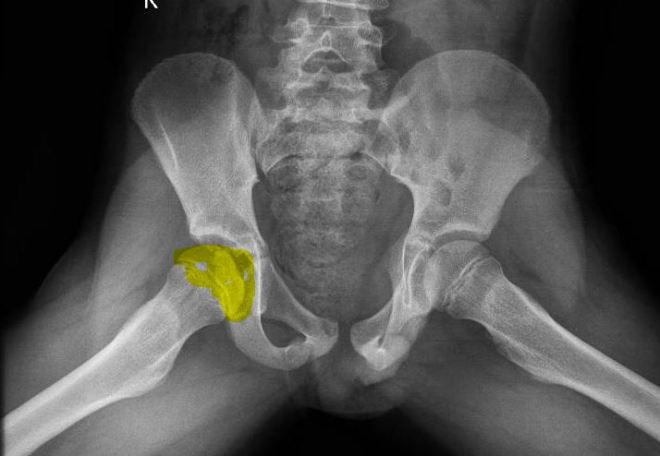

X-ray Lateral view